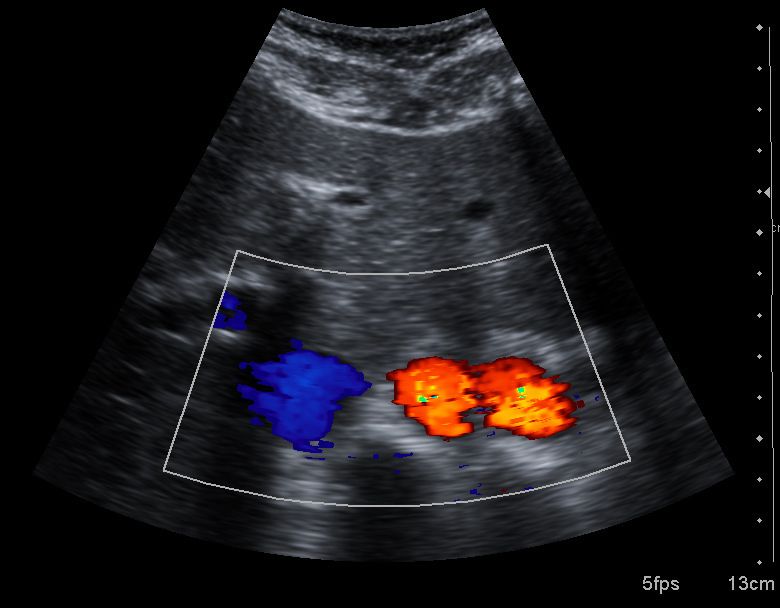

PET扫描图像:通过探测正电子湮灭产生的γ光子对,PET可以显示体内代谢活动的分布

超声成像伪像:主动脉重复伪影(duplication artifact),由多次反射等因素导致的常见超声伪像